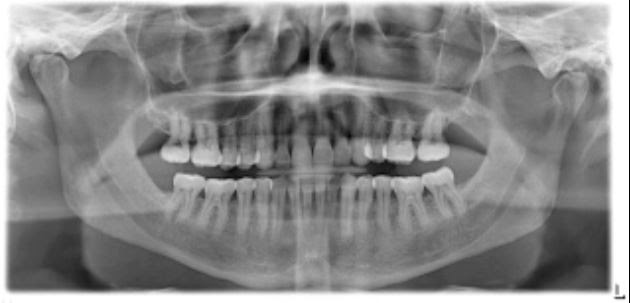

Ask the Dentist – What are the Types of Dental Radiographs Commonly Evaluated at Your Dental Appointment?